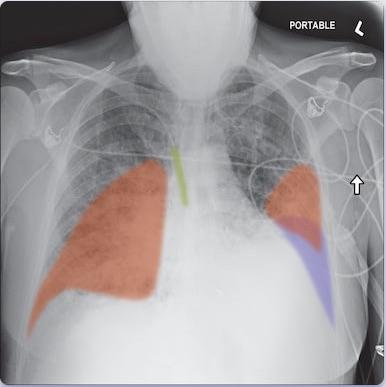

Oxipit ChestEye imaging suite encompasses a fully automatic computer aided diagnosis (CAD) platform which supports 75 radiological findings. The software generates a standardized preliminary text report that incorporates all the radiologically relevant information present in a chest X-ray image. ChestEye imaging suite also features a patient prioritization solution. By automatically arranging scans by urgency it reduces time-to-treatment for time sensitive conditions.

Recently Oxipit introduced AI X-ray longitudinal comparison. The dynamics enables a radiologist to compare X-rays and provide automatically generated reports specifically addressing the changes in images over the course of patient treatment. Oxipit is also developing ChestEye Quality - an automated clinical audit service for retrospective X-ray report analysis, and ChestEye Negative - a service to produce preliminary reports for chest X-ray images with no abnormality.